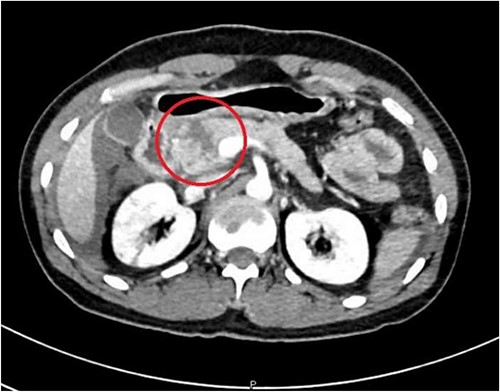

A 36-year-old male manual laborer was assaulted by his roommates (kicked in the abdomen multiple times) and was intoxicated with alcohol. He was writhing in pain, hemodynamically stable with a guarding abdomen. Initial laboratory results showed high serum amylase level 485 U/L, high serum lipase 1200 U/L and elevated liver enzymes. A computed tomography (CT) scan revealed an enlarged bulky head of the pancreas with complete transection of the pancreatic neck (Figs 1–2). In addition, he had a small contusion of the liver and free fluid in the abdomen.

CT abdomen—sagittal section, showing transection of the pancreas (circle).